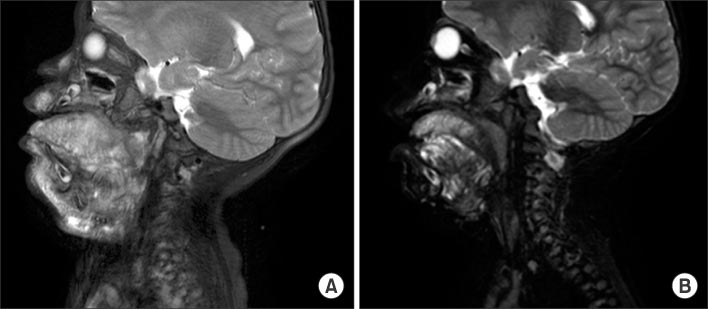

Fig. 5

(A) Sagittal T2-weighted MRI shows cervical lymphangioma which are infiltrating tongue base (patient No. 11). (B) Decreased lymphatic malformation after surgery.

Fig. 5 (A) Sagittal T2-weighted MRI shows cervical lymphangioma which are infiltrating tongue base (patient No. 11). (B) Decreased lymphatic malformation after surgery.